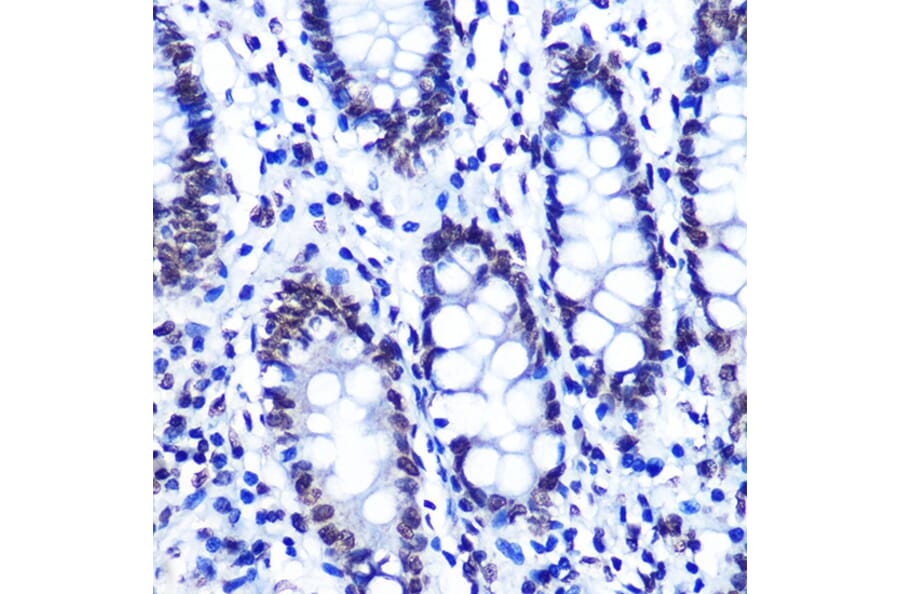

Immunohistochemistry analysis of paraffin-embedded human colon tissue using Anti-SMC1A (phospho Ser957) Antibody [ARC1606] (A306127) at a dilution of 1:100 (40x lens). Perform microwave antigen retrieval with 10 mM Tris/EDTA buffer pH 9.0 before commencing with IHC staining protocol.